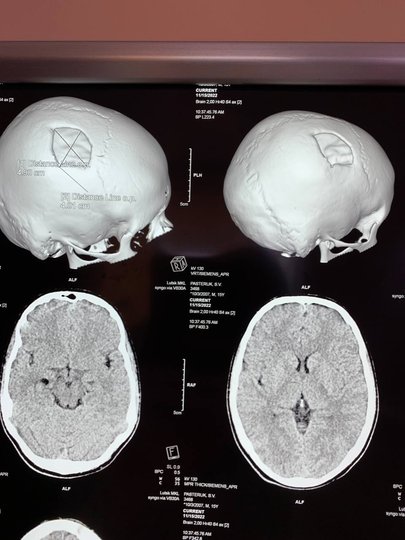

Хірурги регіональної дитячої лікарні Рівн працювали над 15-річним підлітком із складною травмою голови. Він був встановлений на черепі титанового пластику, який захистить мозок від пошкодження.

За даними прес-служби регіональної дитячої лікарні, Рівн, 15-річний хлопець з Вониї, отримав травму дев'ять місяців тому. За яких обставин це сталося, не вказує. Внаслідок травми, частина черепа повинна була бути закрита титановою пластиною – ця операція називається “краніопластика”.

ЩоПошкоджена частина черепної коробки закрита спеціальною титановою пластиною, яка повторює кісткові структури черепа, захищає мозок від пошкодження. Проводили хірургію“, Це сказано У повідомленні.

Відомо, що операція була успішною, хлопець був звільнений додому на третій день.